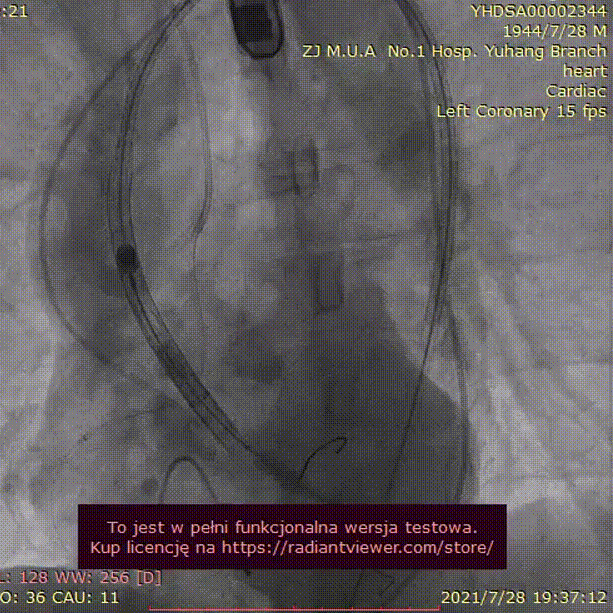

病例2 - 烟囱支架冠脉保护下 Type 0 型二叶瓣

男性,77岁,因“活动后胸闷气促”1月入院。

手术难点及策略:

该病例为Type-0 型二叶瓣,瓣叶长度较长,右冠冠脉风险高,拟在冠脉保护下行TAVR,拟23mm球囊预扩,植入TAV 24号瓣膜。

手术过程:

23mm球囊预扩

(有腰征,无瓣周漏,右冠开口阻塞)

TAV24 瓣膜释放前定位

释放4.0*30mm烟囱支架

植入后造影

术后压差1mmHg

术中经食道心超评估: